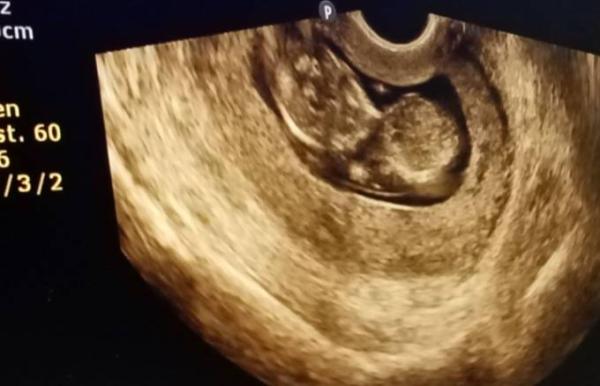

Hey gerade aus mein da Zyste weg und hämatom auch. Könnt ihr das Geschlecht erkennen?

Nein sie sagte nur eine tendenz und das darf sie mir nicht sagen weil ich erst 11+2 bin

Denke auch das es noch zu früh ist um es sicher sagen zu können, ich bin genauso weit wie du und habe am Mittwoch im Kh Termin... Bin auch schon so gespannt Letztes Mal haben sie gesagt Tendenz zum jungen, hat auch gestimmt Lg

Also ich erkenne nicht viel und hab auch keine Ahnung. Aber ich bin beeindruckt, was sich sich aus einer befruchteten Eizelle entsteht. Ich bin sehr gespannt auf nächste Woche Mittwoch, was aus unserem kleinen Pünktchen so geworden ist.